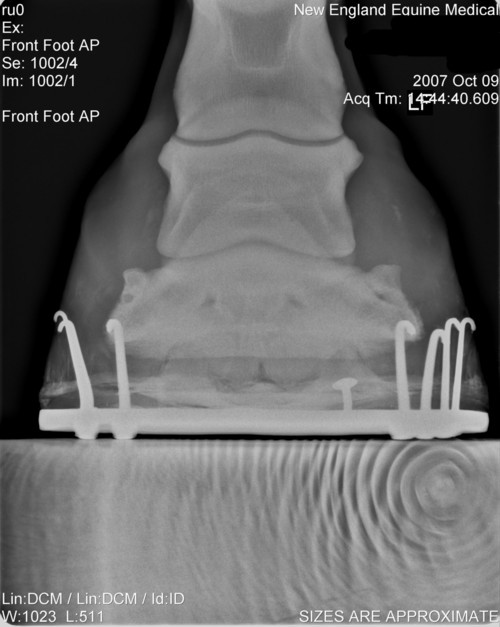

Here are his xrays from about 10-12 weeks ago after the first corrective shoeing. Also included picture of his feet last year before any problems.

Last year

Left AP

Left lat

Right AP

Right Lat

Though I will measure it later, the coffin bone' solar surface angle is acceptable as shod and it should be noted this value does vary greatly among normal horses. Note this is not the same as saying there has been no rotation since the farrier has adjusted the angle with a pad and could have rasped the front wall parallel. We just do not have the information to judge.

Breakover, which is about a cm or two in front of the tip of the coffin bone, looks pretty good though I would prefer a lot more slope to the rocker like that seen in a natural balance shoe. The breakover point of these shoes would disappear on soft ground as the shoe sinks and breakover moves forward to the tip of the foot. Julie would then be right with breakover well too far forward.

Although these images demonstrate the lack of heel and the attempts to correct it, at least the appearance 60 days ago, I would still like to see current images of the foot and sole itself. Your old farrier is correct if the horn quality of the wall is poor and/or the wedges overload the heels. The wedges will distort and breakout poor quality horn and pressure overload slows the growth of the wall at these points. I also do believe egg bars help support poor quality heels when used with proper trimming principles and horn care for more on the trimming see Diseases of Horses » Lameness » Diseases of the Hoof » Correcting Long Toe Low Heel Foot Conformation.